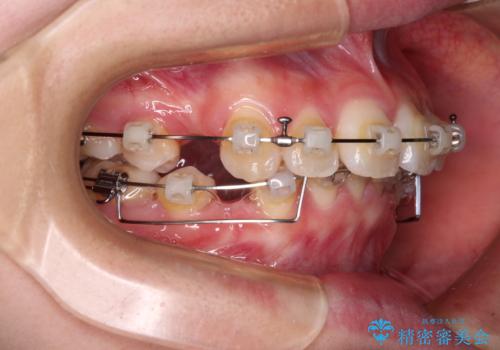

- クリアブラケット

- 3年9ヶ月

- 前に傾斜して飛び出した上顎前歯を気にして来院された患者様です。

上下前歯の前後差が大きく、下顎前歯が隠れるほど深い咬合で、咬合力が強い状態でした。

口元の突出感を改善するために、上下左右の第一小臼歯4本を抜歯し、ワイヤー装置にて矯正治療を行うこととしました。

深い咬み合わせの改善に時間がかかりましたが、下顎前歯がしっかりと見えるまでに整えることができ、口元の突出感も大幅に改善することができました。